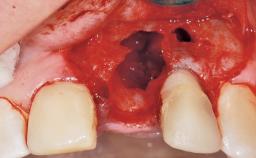

A 42-year-old female patient was referred to our clinic at the School of Dentistry of the University of São Paulo in November 2004, presenting a deficient restoration in the upper left central incisor. The clinical examination revealed no gingival retraction or any signs of gingival inflammation and, therefore, previous periodontal treatment was not considered. The patient presented a high lip line at full smile and a thin tissue biotype. This combination characterized a high-risk situation from an anatomic point of view, which required careful preoperative planning and cautious surgical execution.

Placement Protocol Immediate implant placement

Tooth Site Maxillary incisor or canine

Socket Morphology Single-root socket

Socket Integrity Sufficient, with intact bone walls